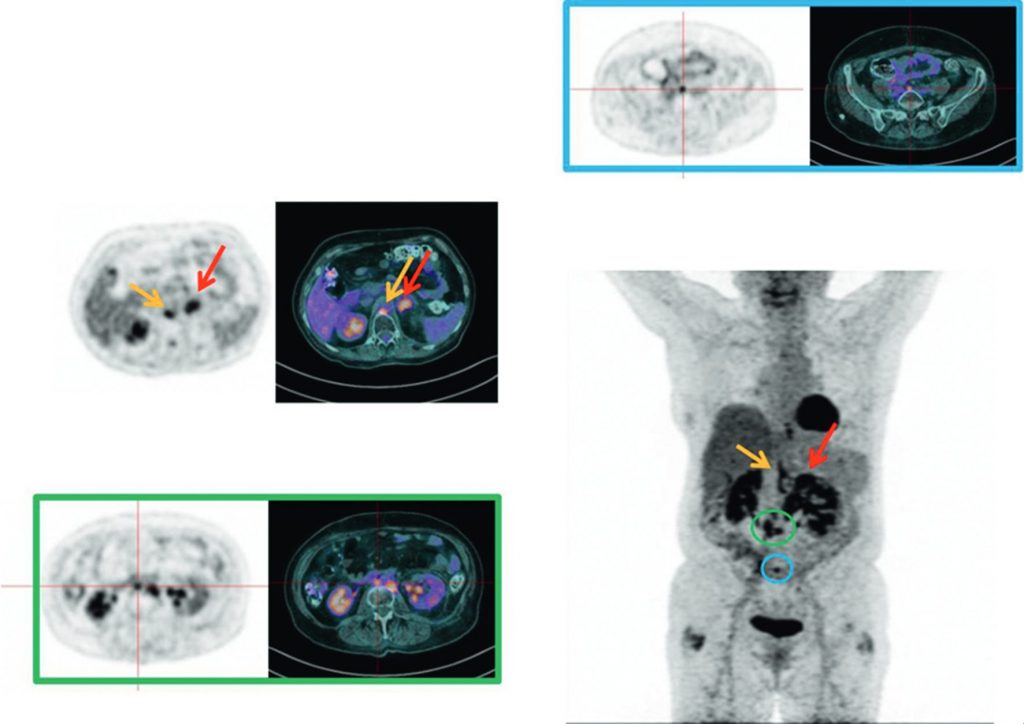

La TEP-TDM au 18FDG peut être indiquée dans le bilan d’extension du cancer de l’endomètre en cas de risque élevé de cancer métastatique (figure 22.1). En revanche, tout comme l’IRM, pour établir le diagnostic, la TEP au FDG n’est pas recommandée.

Fig. 22.1 Bilan d’extension par TEP au 18FDG d’un cancer de l’endomètre à risque élevé de métastases.

Découverte d’une atteinte surrénalienne gauche (flèche rouge), ganglionnaire lombo-aortique gauche (flèche orange), inter-aortico-cave (encadrée en vert) et iliaque commune droite (encadrée en bleu).

Source : CERF, CNEBMN, 2022.

- La TEP-TDM au 18FDG peut être proposée dans le bilan d’extension du cancer de l’endomètre stade ≥ FIGO II.